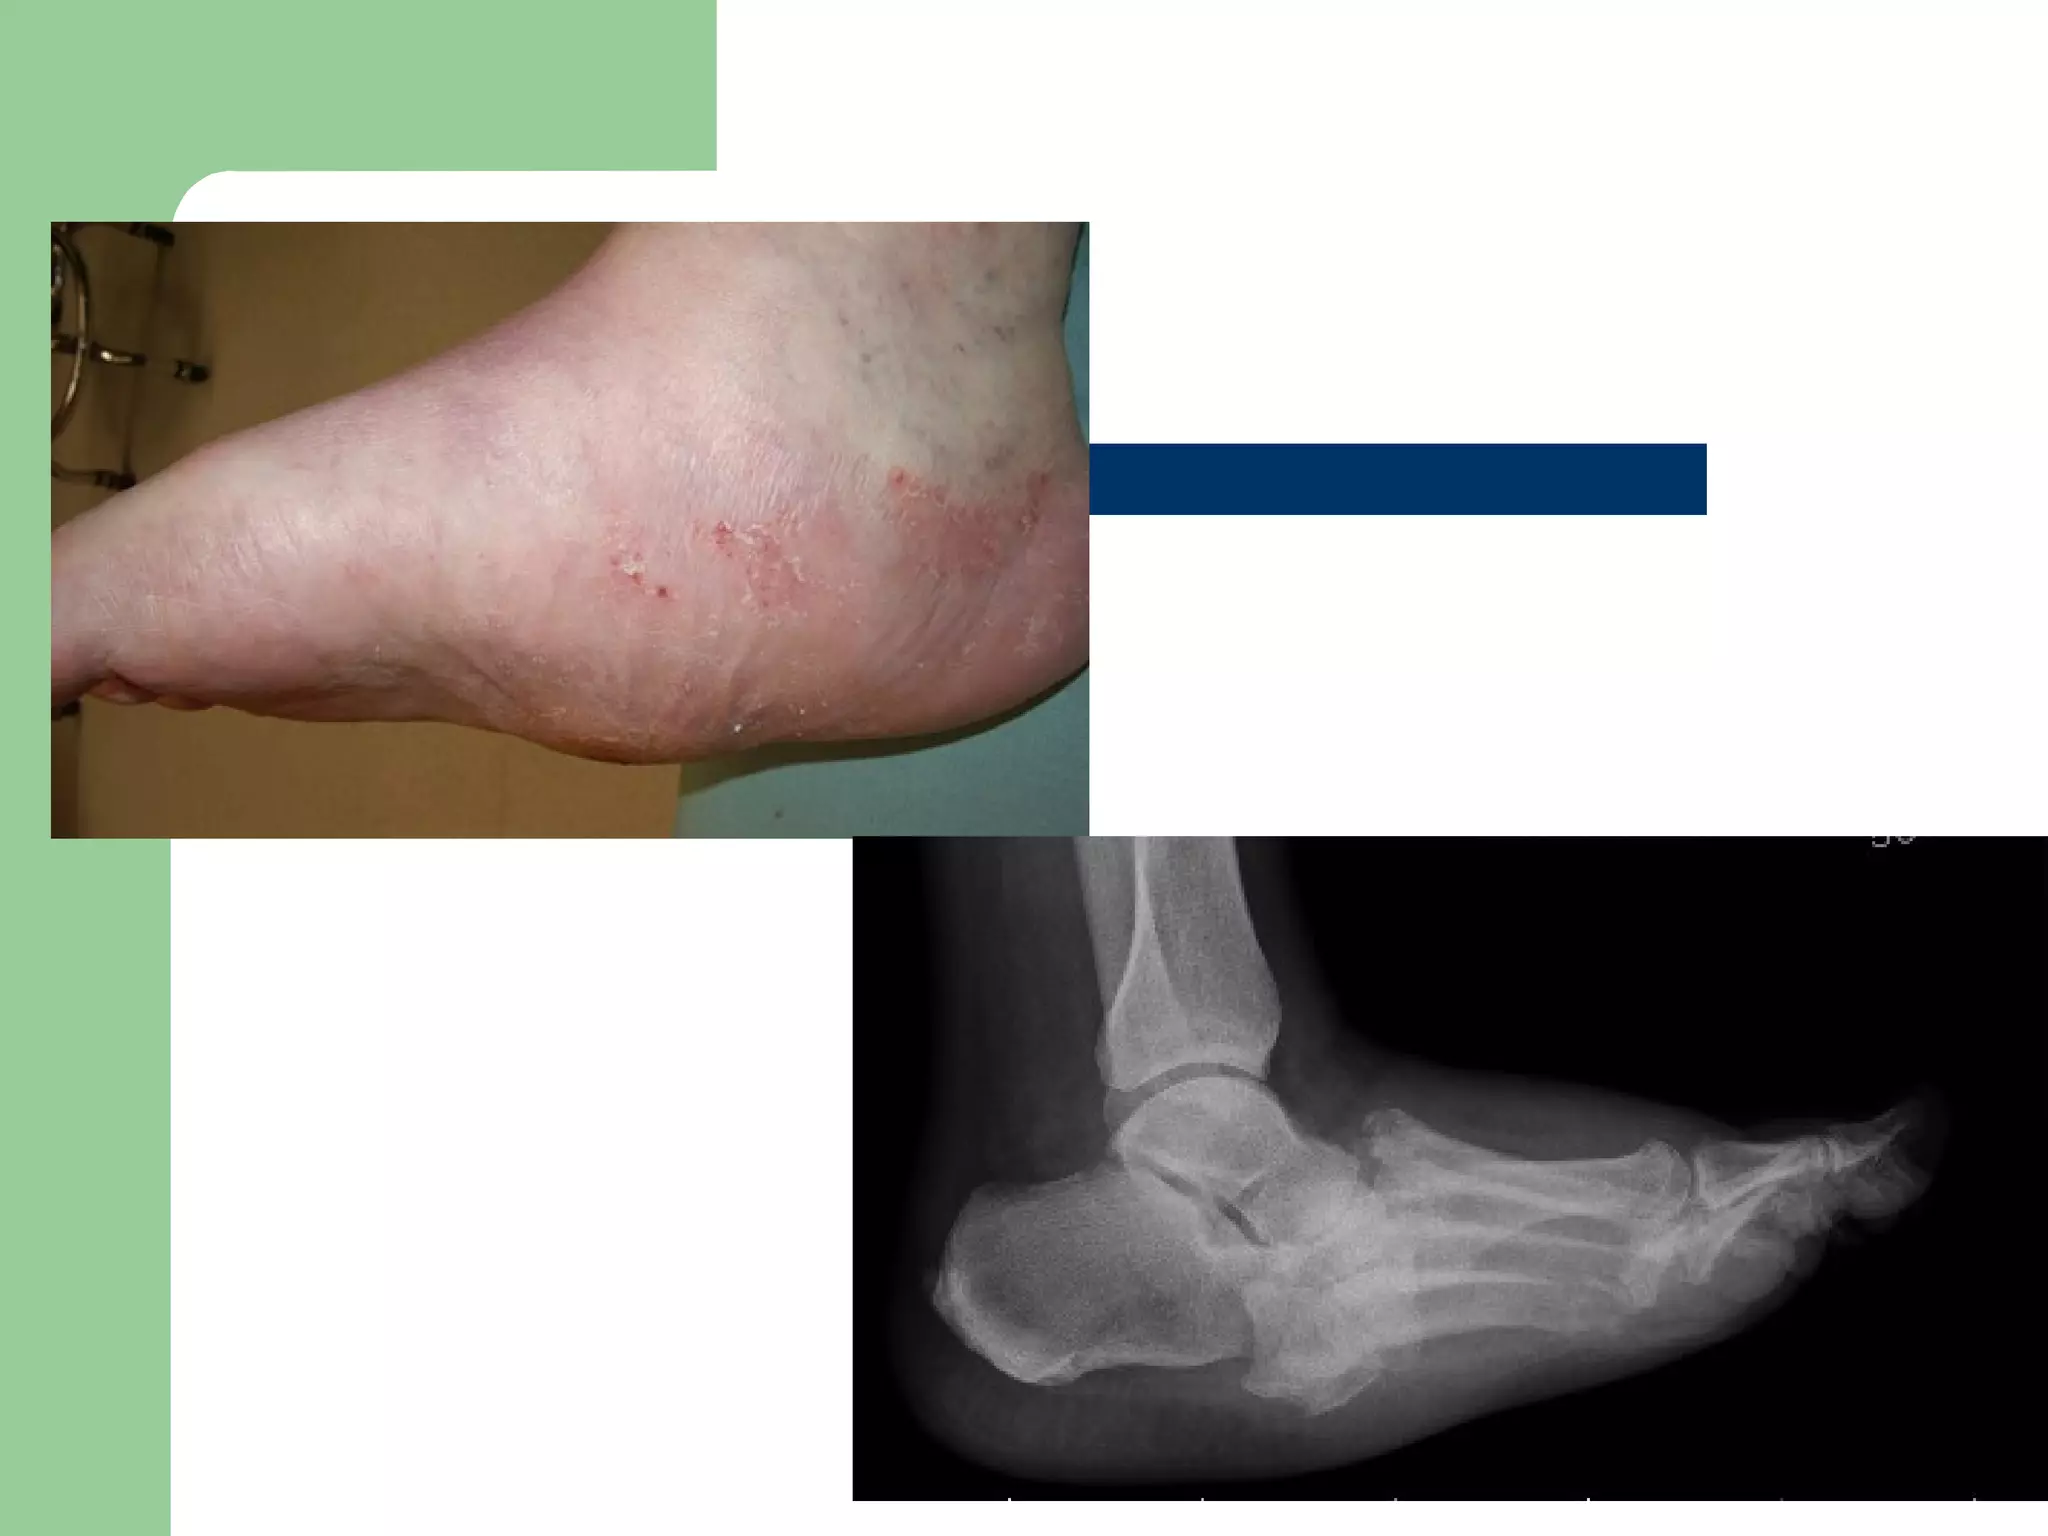

 With the Lisfranc pattern, breakdown initially occurs along the medial column,

with late changes progressing to the lateral column. The arch abducts and

prominences develop, leading to deformity, fullness, and ulceration. The

naviculocuneiform pattern leads to collapse at the naviculocuneiform joint, with

development of a lateral rocker-bottom deformity. The perinavicular pattern is

caused by osteonecrosis or fracture of the navicular. The lateral arch height

decreases, leading to a lateral rocker and shortening of the medial column.

Eventually this breakdown progresses to the central aspect of the foot, with

severe plantar flexion of the talus and eventual ulceration. The transverse tarsal

pattern is caused by lateral subluxation of the navicular on the talus and

abduction of the foot with a valgus calcaneus. Calcaneal pitch eventually

decreases, and a central rocker develops at the calcaneocuboid joint. In late

stages, the talus is completely dislocated from the navicular, and ulceration

develops at the calcaneocuboid interval. All four patterns eventually progress to

a rocker-bottom deformity and chronic ulceration.

 With theLisfranc pattern, breakdown initially occurs along the medial column, with late changes progressing to the lateral column. The arch abducts and prominences develop, leading to deformity, fullness, and ulceration. The naviculocuneiform pattern leads to collapse at the naviculocuneiform joint, with development of a lateral rocker-bottom deformity. The perinavicular pattern is caused by osteonecrosis or fracture of the navicular. The lateral arch height decreases, leading to a lateral rocker and shortening of the medial column. Eventually this breakdown progresses to the central aspect of the foot, with severe plantar flexion of the talus and eventual ulceration. The transverse tarsal pattern is caused by lateral subluxation of the navicular on the talus and abduction of the foot with a valgus calcaneus. Calcaneal pitch eventually decreases, and a central rocker develops at the calcaneocuboid joint. In late stages, the talus is completely dislocated from the navicular, and ulceration develops at the calcaneocuboid interval. All four patterns eventually progress to a rocker-bottom deformity and chronic ulceration.